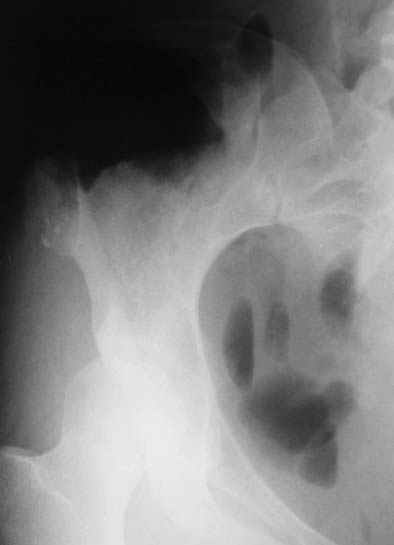

Уважаемые коллеги! К нам поступила пациентка 16 лет с диагнозом: остеохондрома крыла правой подвздошной кости.

Судя по КТ, проблема не в гребне а в крыле...

Опухоль имеет задне-наружное нправление...

По-моему, КТ-картина наводит на мысль об озлокачествлении (резкая неоднородность, местами размытие контуров) - вторичной хондросаркоме. Местами, кстати, имеется рост и в направлении брюшной полости. Для решения вопроса об объеме резекции в данном случае оправдана трепанобиопсия. Если это хондросаркома, особенно низкодифференцированная, то стоит обсудить возможность удаления всего крыла с окружающими мягкими тканями. Вариант реконструкции - комбинированная пластика аллотрансплантатами. А вот какими - зависит от наличия костного банка и возможностью индивидуального изготовления трансплантатов. При отсутствии таковой не лучше ли направить ее в ЦИТО?